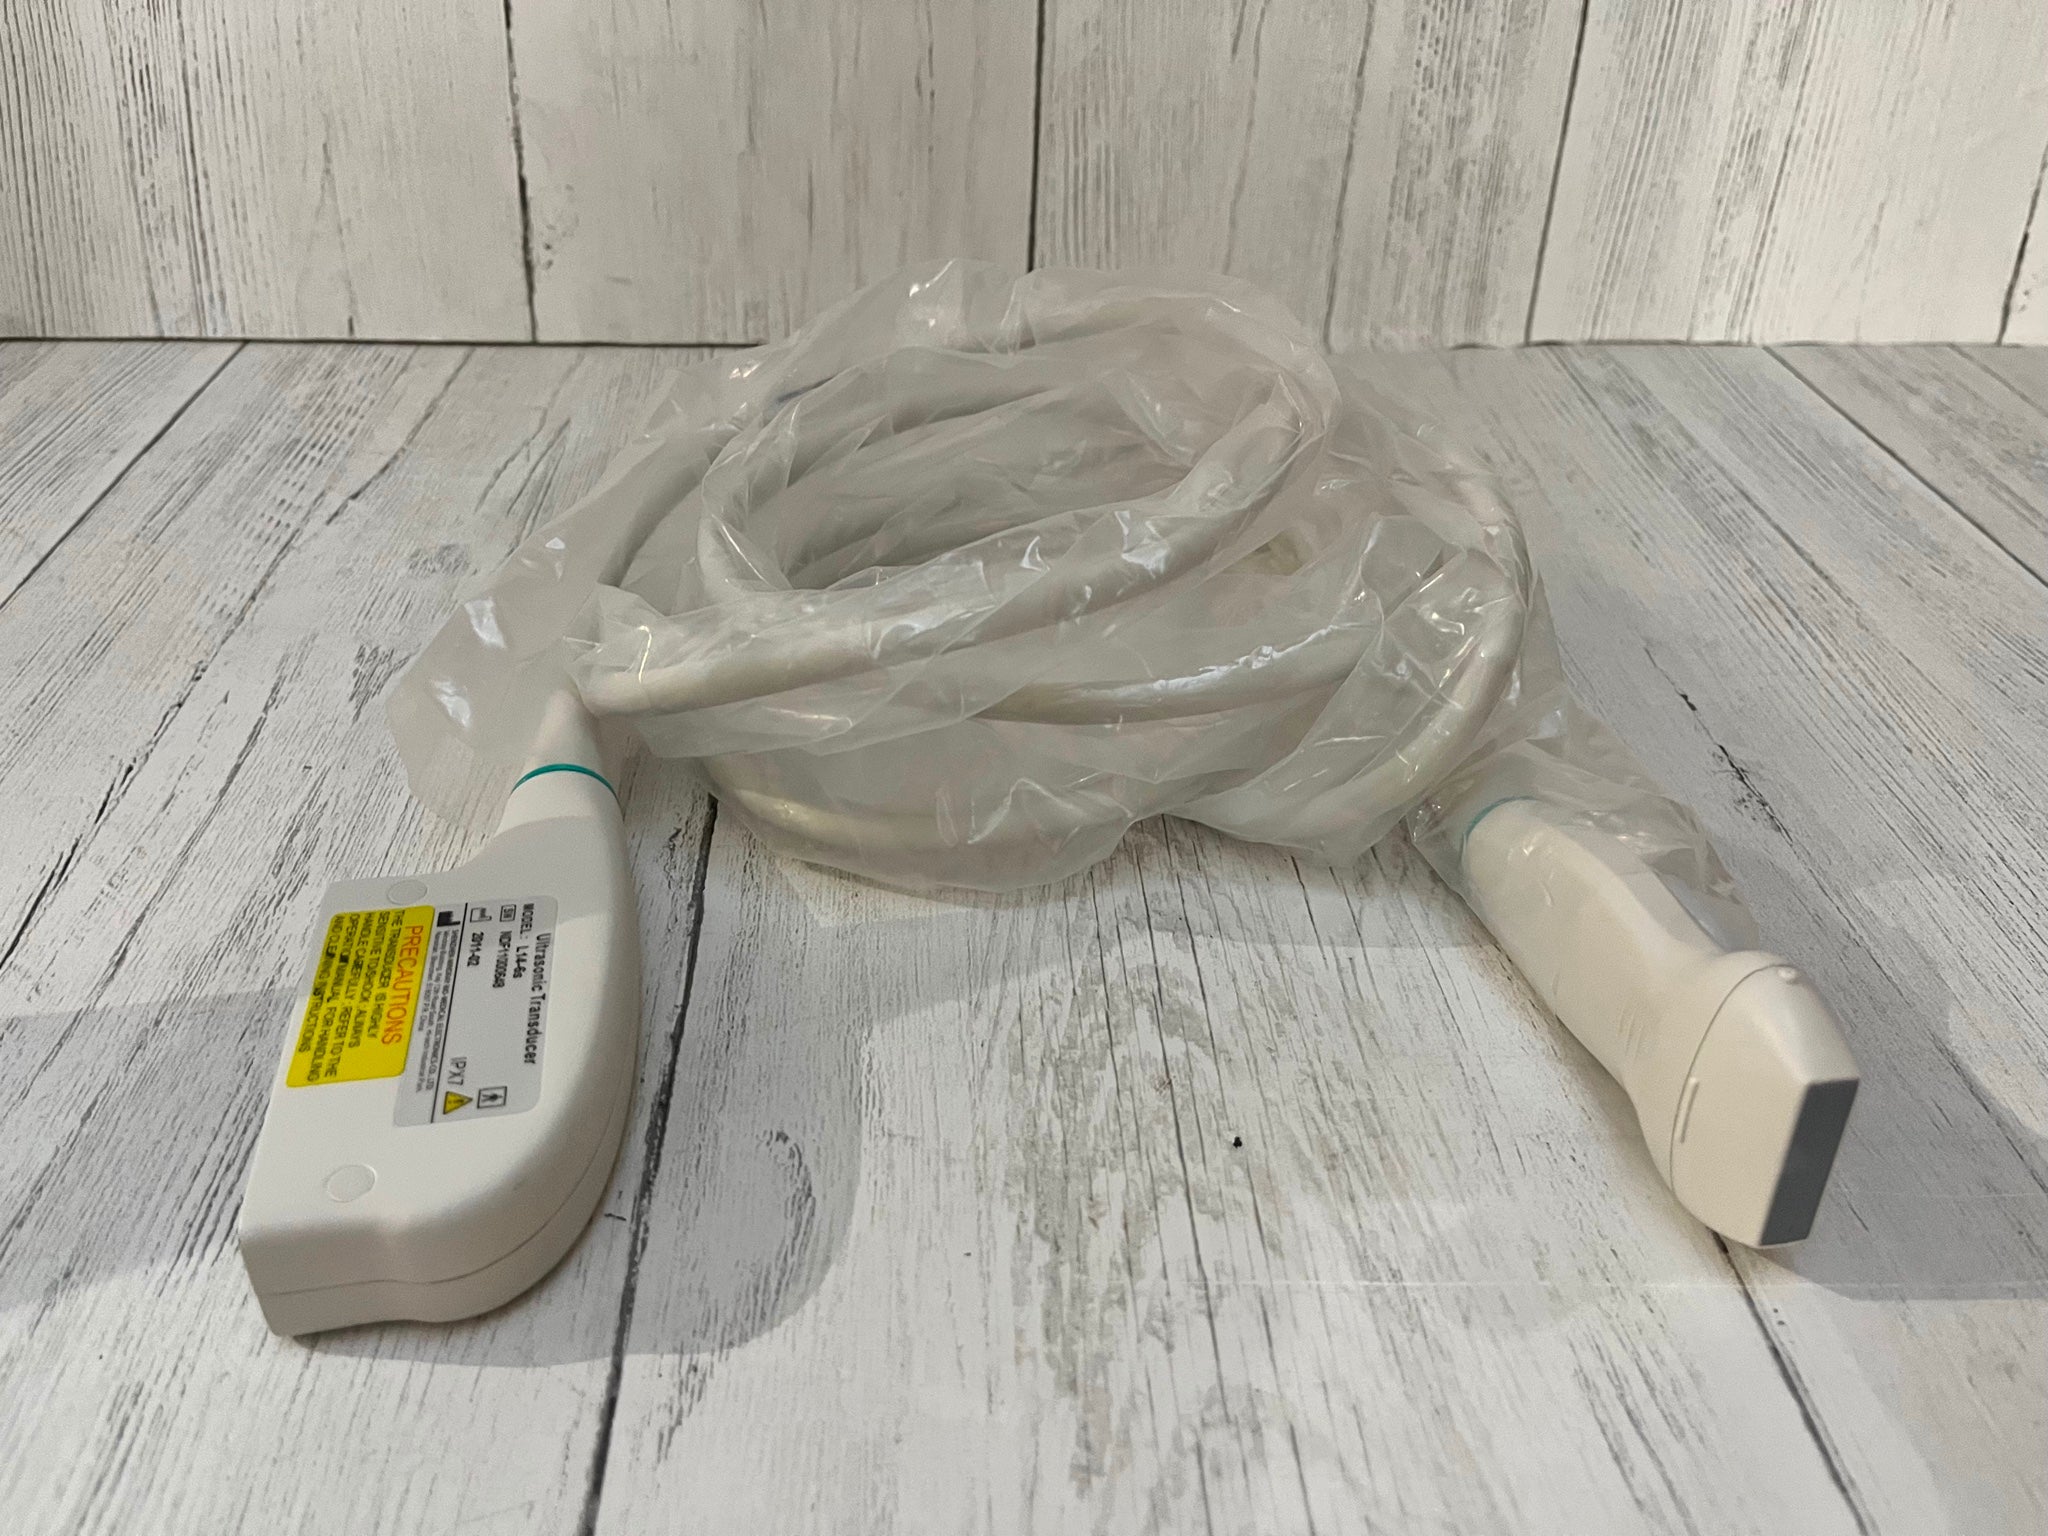

The Laptop Ultrasound Scanner is designed to provide clear and precise imaging, making it an essential tool for healthcare professionals. This device offers advanced functionality, allowing doctors to perform a wide range of examinations. Because it includes a transvaginal probe, it is particularly effective for gynecological assessments, ensuring accurate diagnosis.

Portability and Convenience